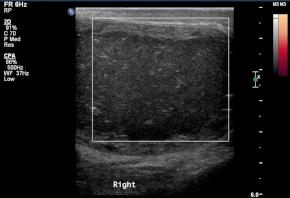

• A large low echoic mass in Rt scrotum and non-visualization of normal Rt testis

• No internal blood flow even on power doppler image

Comments Difficult to diagnose due to the lack of a characteristic \"onion-skin\" shape and non-visible normal testicle.